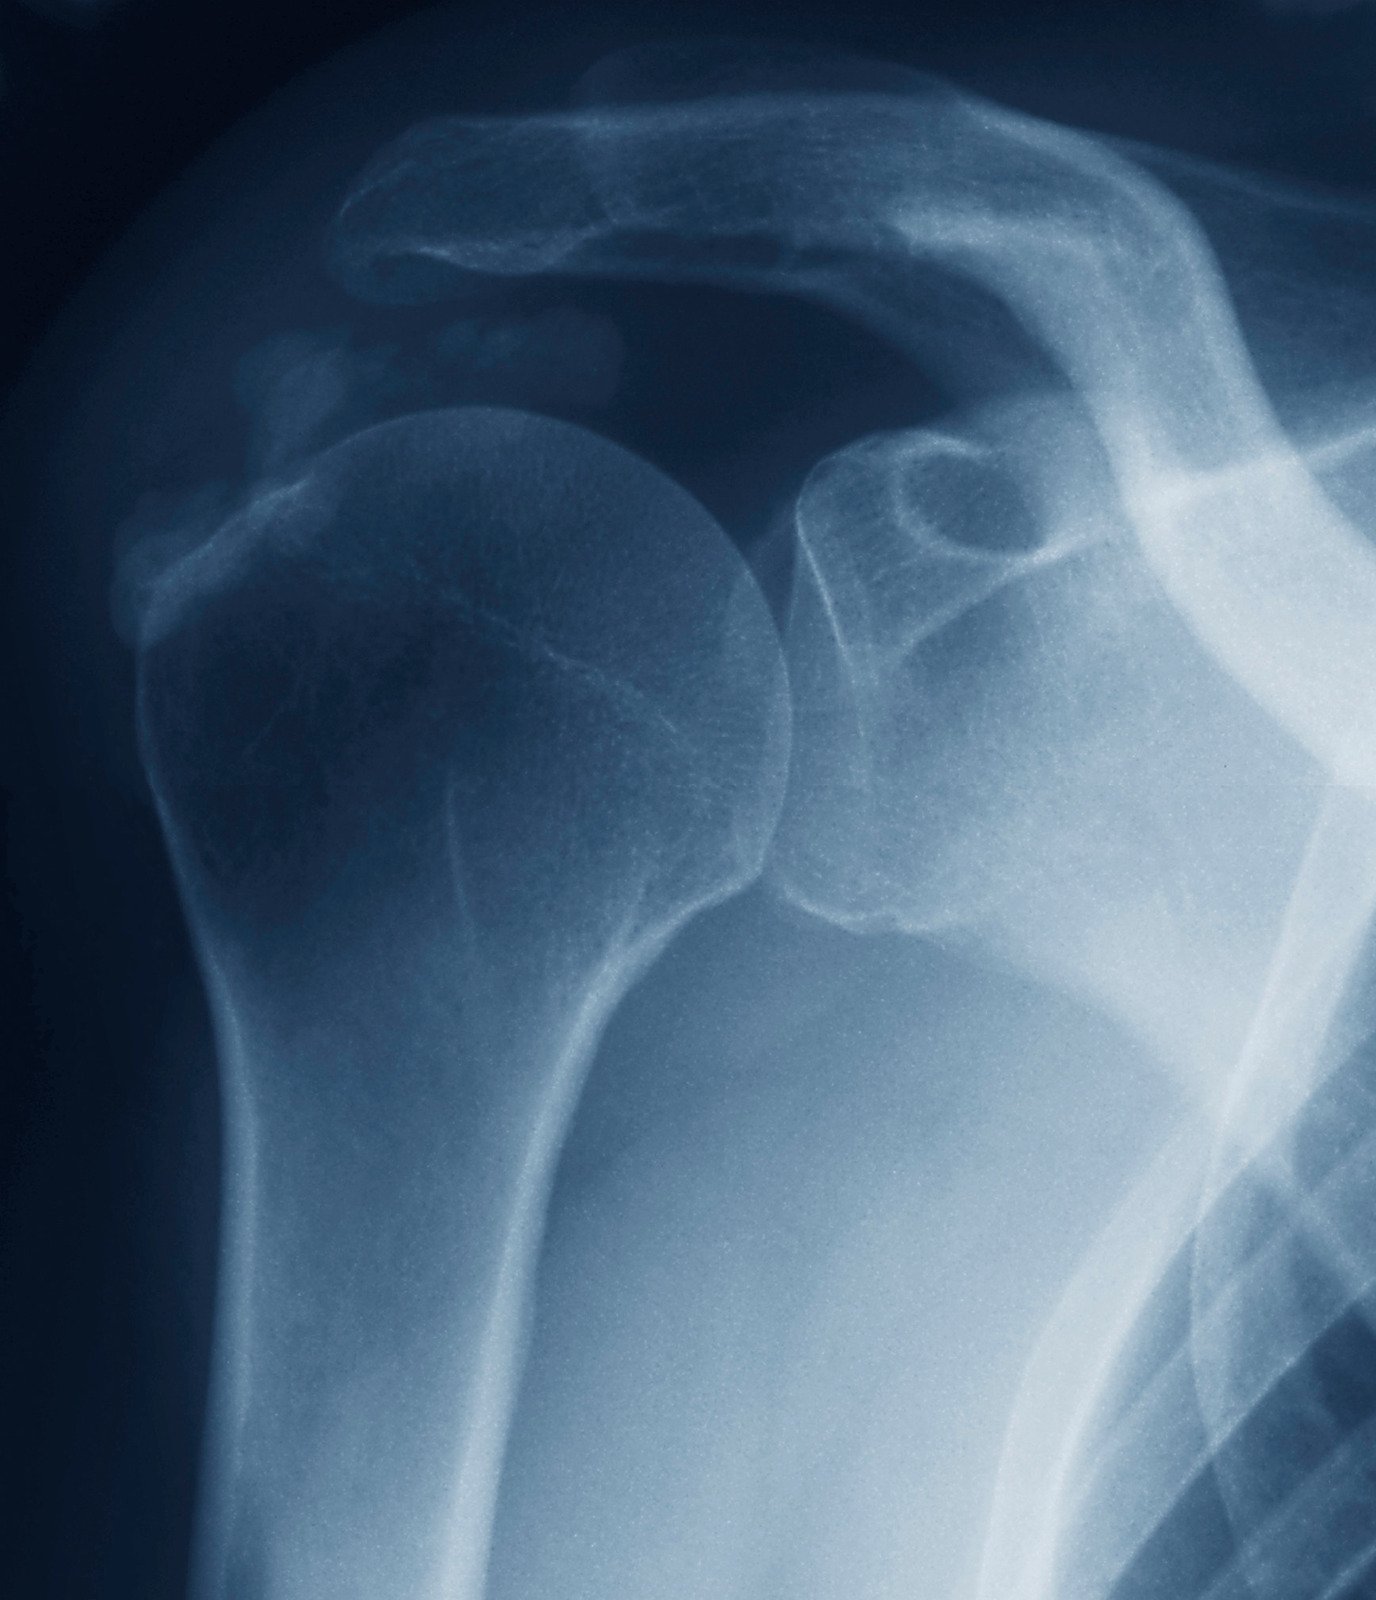

X-ray 검사

칼슘이 축적된 부위를 확인하는 가장 기본적인 검사입니다. X-ray를 통해 힘줄 내의 석회화가 보입니다.